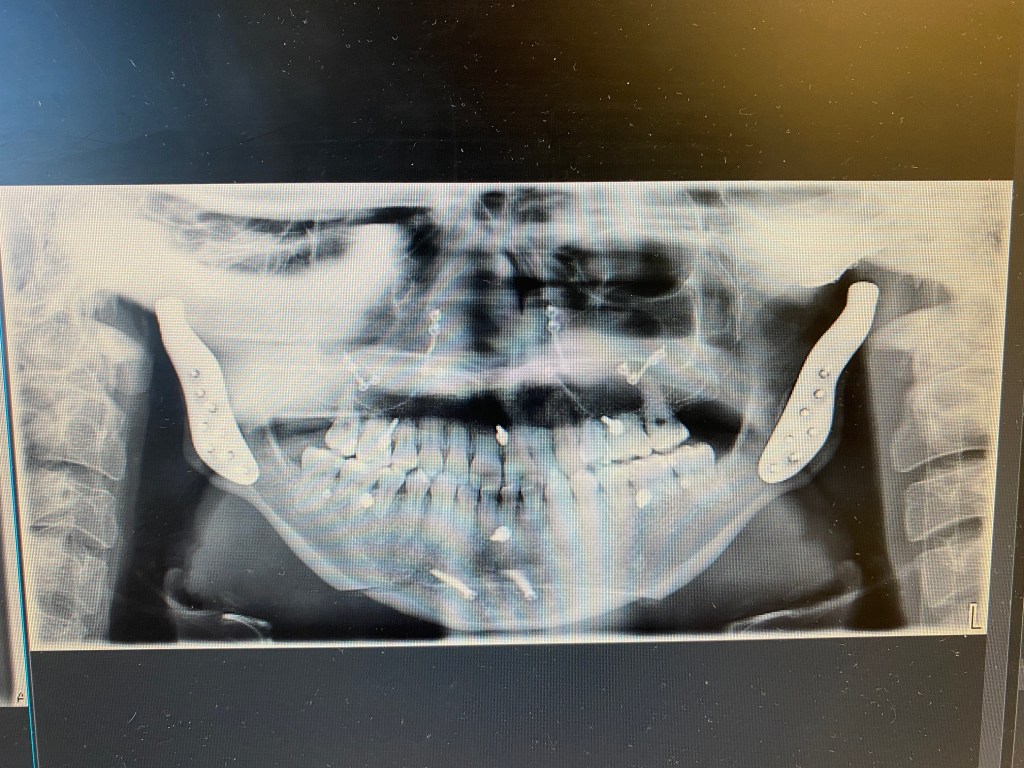

10 | Checkup Appointment

Today I had my 10 day post-op appointment with Dr. Sullivan and was greeted with a cool surprise – the surgeon who invented the surgical counter clockwise rotation of the mandible was there, Dr. Johan Reyneke. Dr. Sullivan had reached out to him awhile back in his career while Dr. Reyneke was working in South…